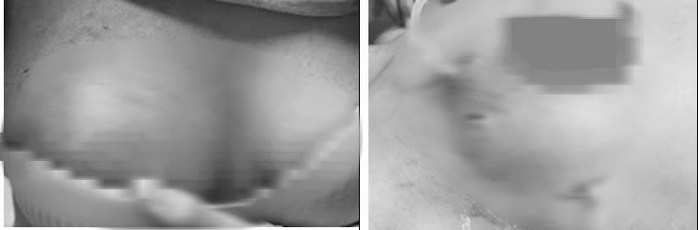

Hình ảnh sưng, đau vùng ngực (ảnh trái) và hình ảnh sau phẫu thuật tháo mủ, nạo bỏ tổ chức hoại tử.

Qua thăm khám và thực hiện các xét nghiệm cần thiết, bác sĩ chẩn đoán bệnh nhân bị áp-xe vú phải sau tiêm filler, một biến chứng nghiêm trọng của việc tiêm chất làm đầy không đảm bảo an toàn.

Người bệnh được chỉ định phẫu thuật lấy bỏ mô tuyến vú và mô mỡ hoại tử, dẫn lưu khoảng 150 ml hỗn dịch mủ và tổ chức hoại tử, đồng thời đặt dẫn lưu để bơm rửa khoang áp xe. Hiện tình trạng bệnh nhân đã ổn định và tiếp tục được theo dõi, điều trị.